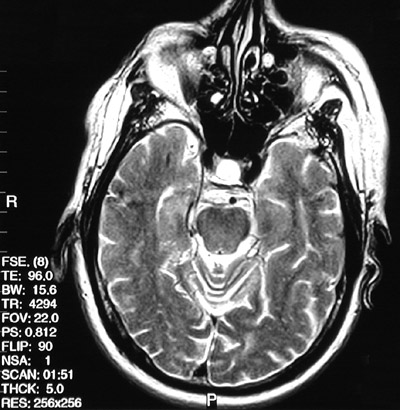

![]() | The FSE T2 weighted MRI scan in axial view above demonstrates bright fluid filling the sella turcica, indicative of an empty sella syndrdome. In the T1 weighted post gadolinium view below the sella appears dark. This peculiar syndrome can lead to hypopituitarism. |